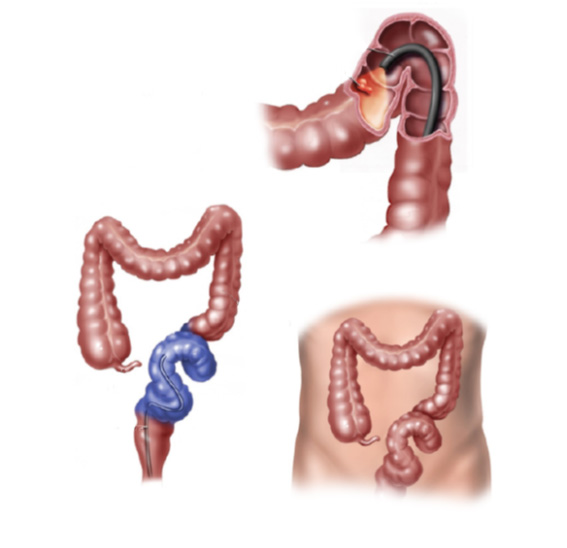

O que é a colonoscopia?

Colonoscopia é o exame endoscópico do cólon (intestino grosso) e muitas vezes também do íleo terminal (porção final do intestino delgado). Além da inspeção da superfície intestinal, a colonoscopia permite também a realização de biópsias que podem ser úteis no estabelecimento do diagnóstico. Procedimentos terapêuticos também podem ser realizados durante a colonoscopia, entre eles o mais frequente é a remoção de pólipos (polipectomia).

A colonoscopia é a forma mais direta e completa para verificar a mucosa do cólon inteiro. Indicada para:

- Prevenção e detecção precoce do câncer de cólon. A colonoscopia pode ajudar a encontrar pólipos, que podem se tornar câncer. Os pólipos podem ser removidos através de polipectomia. O exame também pode permitir que seu médico encontre tumores cancerosos precocemente, quando é mais fácil de ser curado.

- Se você tem mais de 50 anos de idade, deve fazer uma colonoscopia. Se tiver pais ou irmãos que tiveram câncer no cólon, especialmente antes que eles tivessem 50 anos de idade, você pode ter um maior risco de pólipos ou câncer. Neste caso, o seu médico pode querer começar a triagem antes de você ter 50 anos.

- Diagnóstico de alguma doença intestinal. Se você tiver alguns sintomas e ainda não tem o diagnóstico, pode ter que realizar este exame para tentar encontrar a causa. Por exemplo, se você estiver tendo dor abdominal, alteração do hábito intestinal, sangramento pelas fezes, diarreia crônica. Através da colonoscopia seu médico pode verificar se existe alguma irritação na mucosa do intestino que podem justificar estes sintomas.

O que acontecerá durante o exame ?

Após o preparo do cólon, o paciente é levado à sala de exame onde será sedado. A sedação é realizada por via endovenosa e ajuda o paciente a dormir e relaxar. O colonoscópio é então introduzido pelo reto até o ceco (porção inicial do cólon) ou até o íleo terminal (porção final do intestino delgado). Durante a retirada do aparelho é feita uma minuciosa inspeção identificando as eventuais alterações.

Se necessário, pequenas amostras de tecido (biópsias) podem ser colhidas durante o exame para análise microscópica detalhada. Não se preocupe, não dói. As amostras retiradas durante o exame (biópsias ou pólipos) são enviadas ao laboratório de patologia para análise.

O que é a colonoscopia?

Colonoscopia é o exame endoscópico do cólon (intestino grosso) e muitas vezes também do íleo terminal (porção final do intestino delgado). Além da inspeção da superfície intestinal, a colonoscopia permite também a realização de biópsias que podem ser úteis no estabelecimento do diagnóstico. Procedimentos terapêuticos também podem ser realizados durante a colonoscopia, entre eles o mais frequente é a remoção de pólipos (polipectomia).

A colonoscopia é a forma mais direta e completa para verificar a mucosa do cólon inteiro. Indicada para:

- Prevenção e detecção precoce do câncer de cólon. A colonoscopia pode ajudar a encontrar pólipos, que podem se tornar câncer. Os pólipos podem ser removidos através de polipectomia. O exame também pode permitir que seu médico encontre tumores cancerosos precocemente, quando é mais fácil de ser curado.

- Se você tem mais de 50 anos de idade, deve fazer uma colonoscopia. Se tiver pais ou irmãos que tiveram câncer no cólon, especialmente antes que eles tivessem 50 anos de idade, você pode ter um maior risco de pólipos ou câncer. Neste caso, o seu médico pode querer começar a triagem antes de você ter 50 anos.

- Diagnóstico de alguma doença intestinal. Se você tiver alguns sintomas e ainda não tem o diagnóstico, pode ter que realizar este exame para tentar encontrar a causa. Por exemplo, se você estiver tendo dor abdominal, alteração do hábito intestinal, sangramento pelas fezes, diarreia crônica. Através da colonoscopia seu médico pode verificar se existe alguma irritação na mucosa do intestino que podem justificar estes sintomas.

O que acontecerá durante o exame ?

Após o preparo do cólon, o paciente é levado à sala de exame onde será sedado. A sedação é realizada por via endovenosa e ajuda o paciente a dormir e relaxar. O colonoscópio é então introduzido pelo reto até o ceco (porção inicial do cólon) ou até o íleo terminal (porção final do intestino delgado). Durante a retirada do aparelho é feita uma minuciosa inspeção identificando as eventuais alterações.

Se necessário, pequenas amostras de tecido (biópsias) podem ser colhidas durante o exame para análise microscópica detalhada. Não se preocupe, não dói. As amostras retiradas durante o exame (biópsias ou pólipos) são enviadas ao laboratório de patologia para análise.